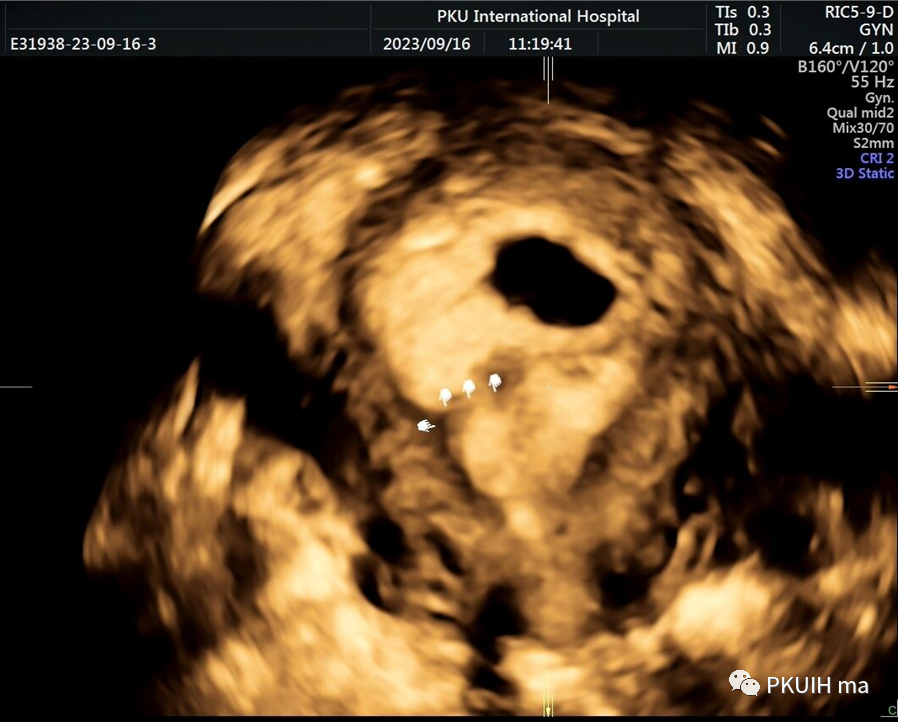

三维超声显示宫内环在子宫内发生扭转

三维超声显示子宫内膜结合带消失(腺肌病的病人)

三维超声显示宫内妊娠囊和宫腔黏连带的关系

三维断层扫描显示整个宫腔结构